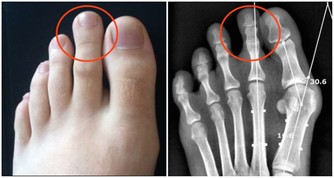

在生活中也有這樣的說法,即豆腐是痛風的“發物”,那麼這種說法到底是不是真的呢?豆腐作為一類常見豆製品,很多人都將其與“高嘌呤”劃等號,但其實並沒有清楚了解到豆腐的嘌呤含量到底有多少。其實豆腐在製作的過程中,往往需要經過研磨以及加水稀釋等工序,在這一過程中,豆腐的嘌呤生成其實是比較少的。

舉個例子來說,每100克的豆腐中大約只含有30毫克的嘌呤物質,是屬於低嘌呤食物類型的,並不是說一吃就會誘發痛風。